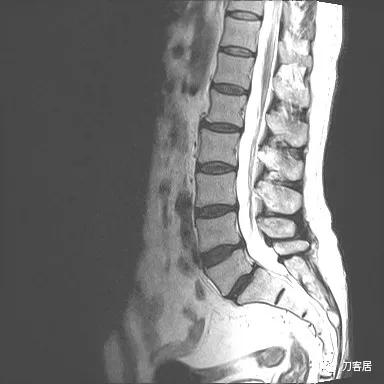

入院后予以腰椎CT及MRI检查,未见明显之椎间盘突出及椎管狭窄。

图11. 20210626术前腰椎MRIT2相1

图12. 20210626术前腰椎MRIT2相2